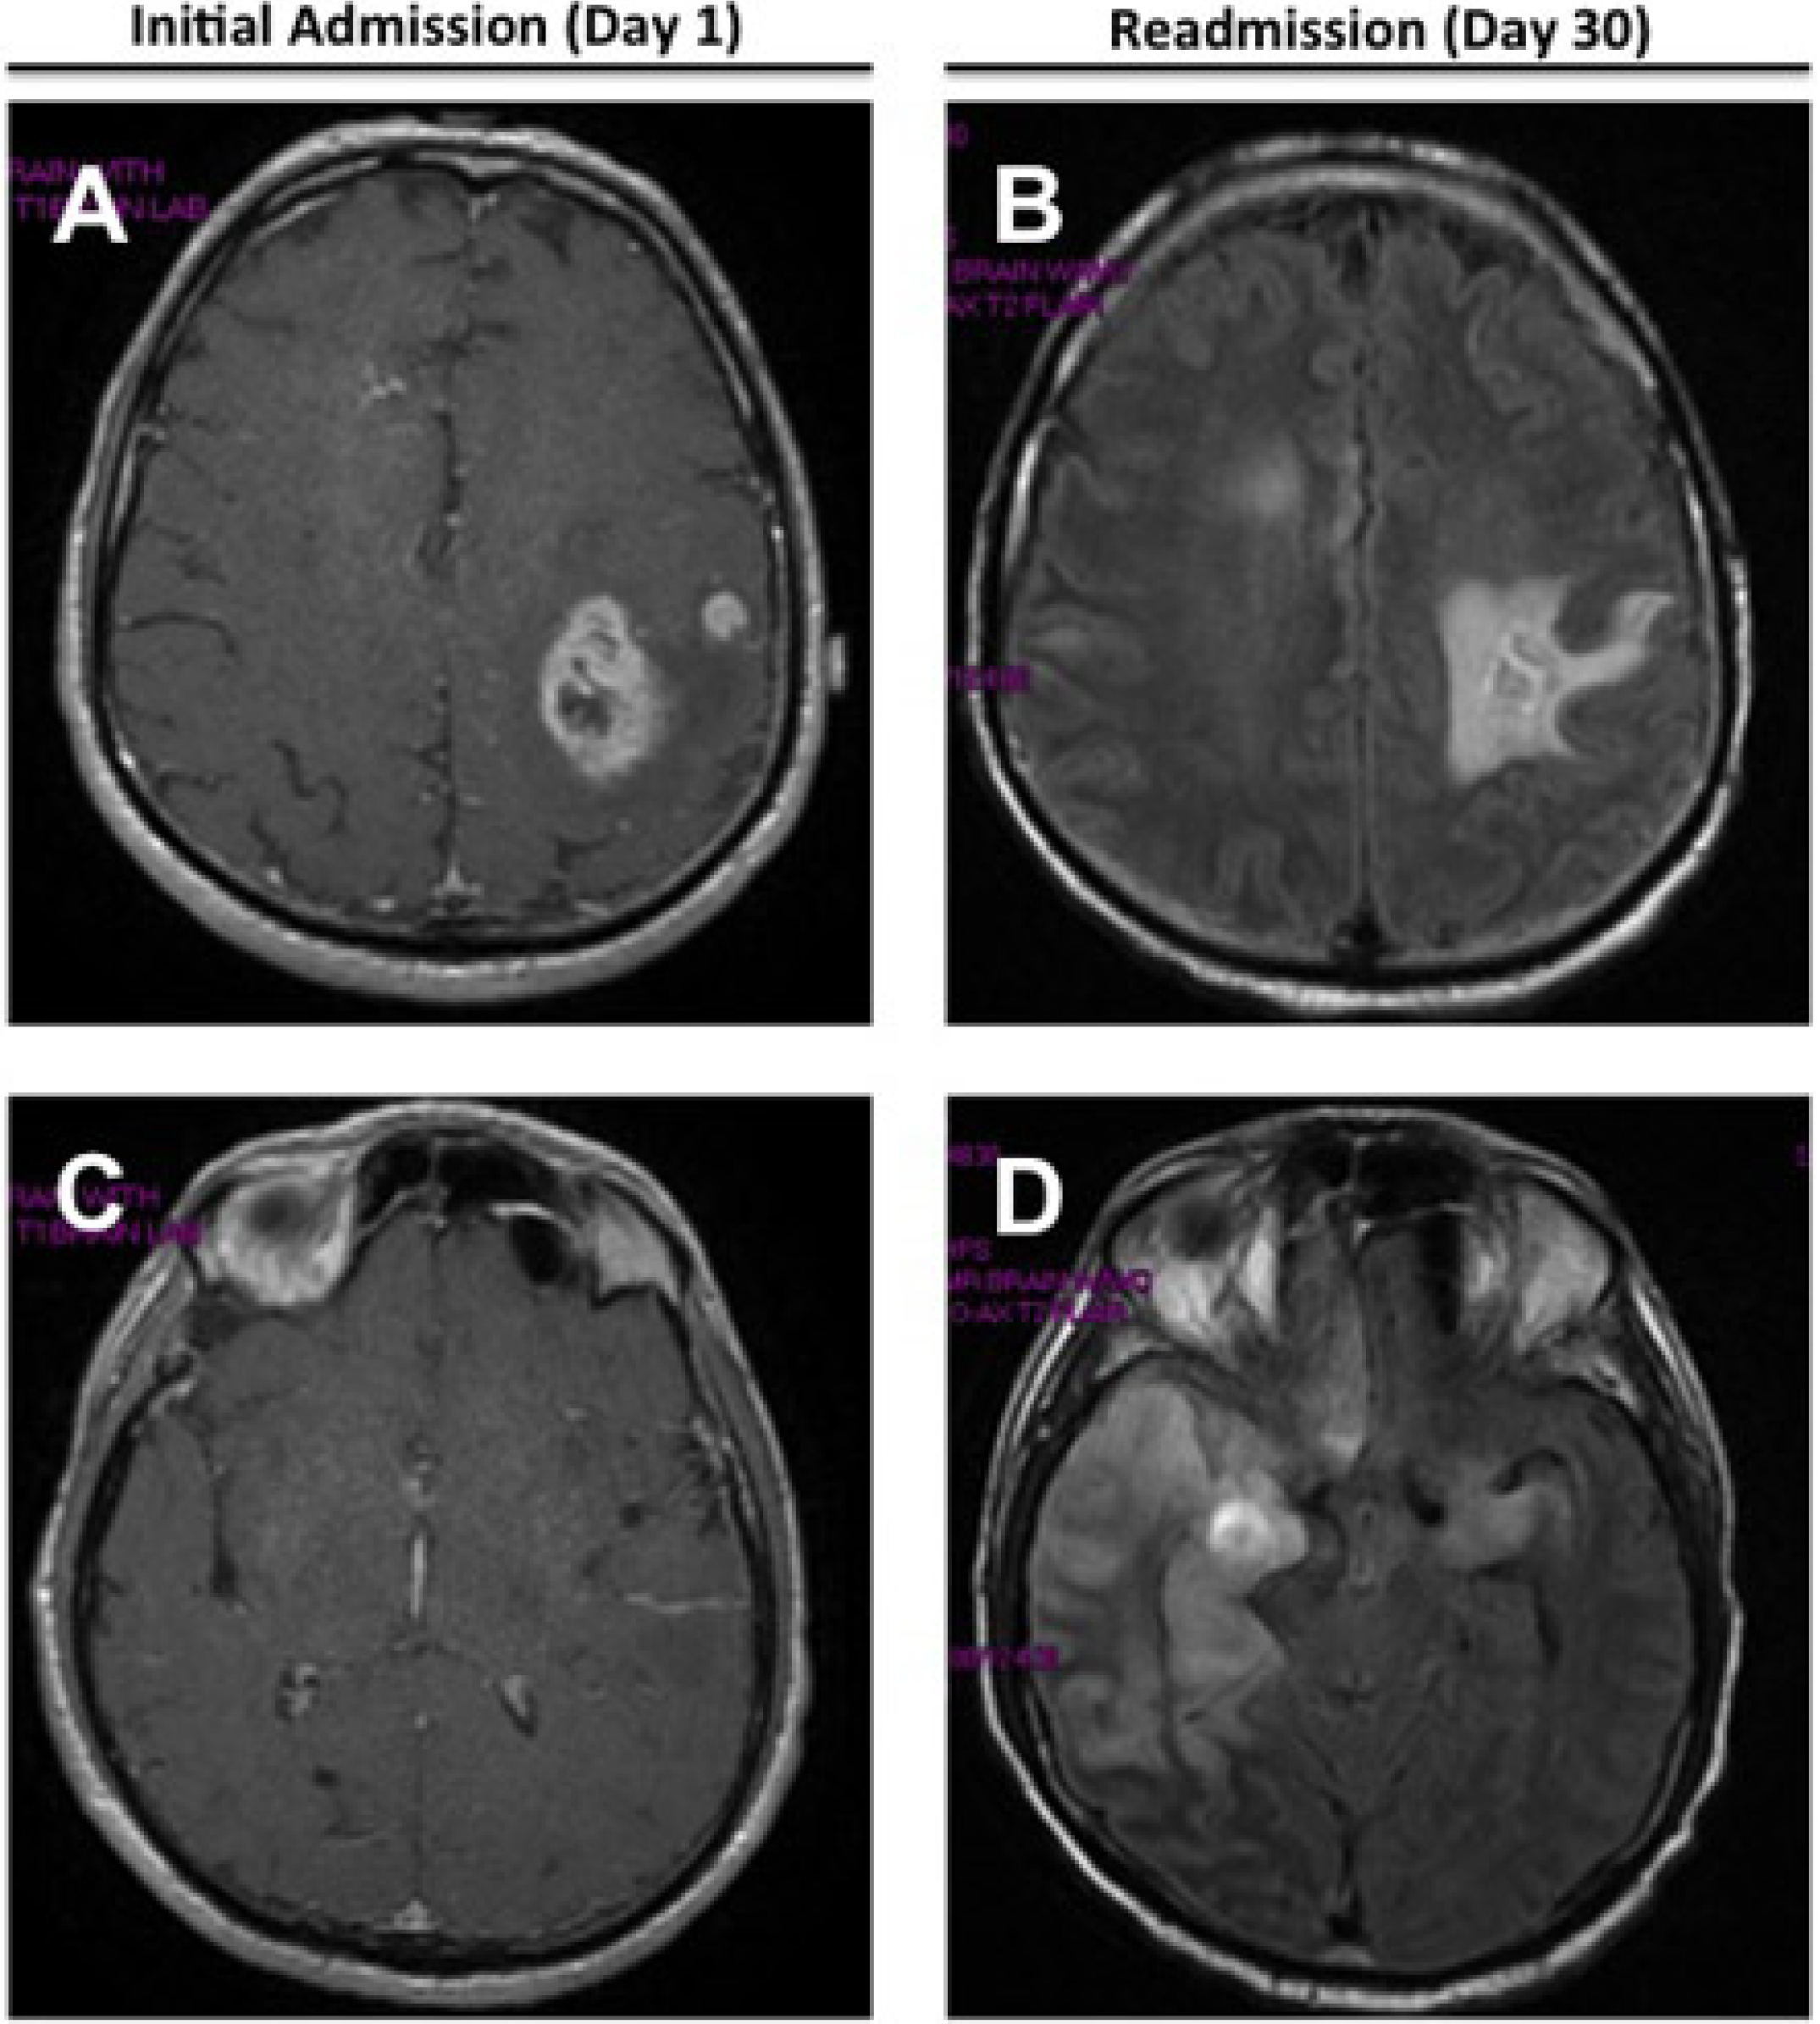

2. Case Presentation

| 13 | Cunha et al., 2014 | 60M | − | 1 month | <5 WBC/mm3 0 RBC/mm3 | Prot = 100 mg/dL Gluc = 33 mg/dL Lactate = 38 IU/L | + | Multiple left temporo-parietal enhancing lesions; subsequent signal abnormality of the right temporal lobe | Generalized background slowing with left frontotemporal low amplitude sharp waves | Transient |